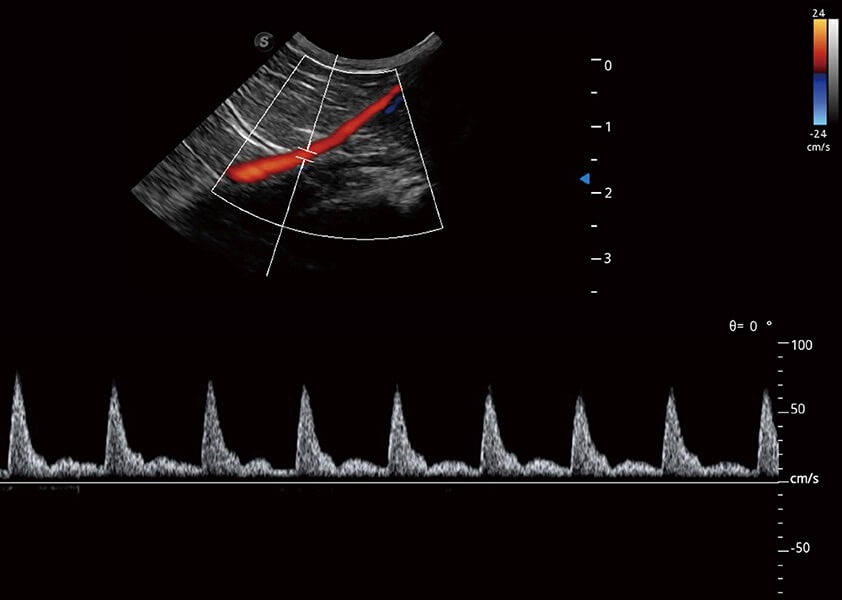

(猫)髂动脉血流频谱